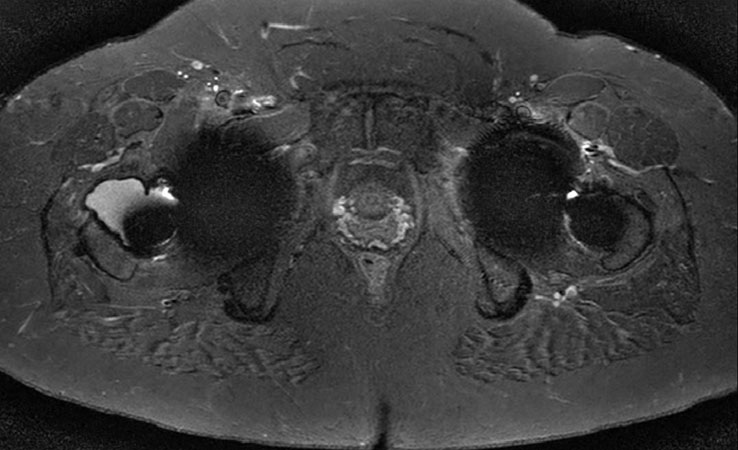

Axial STIR MARS